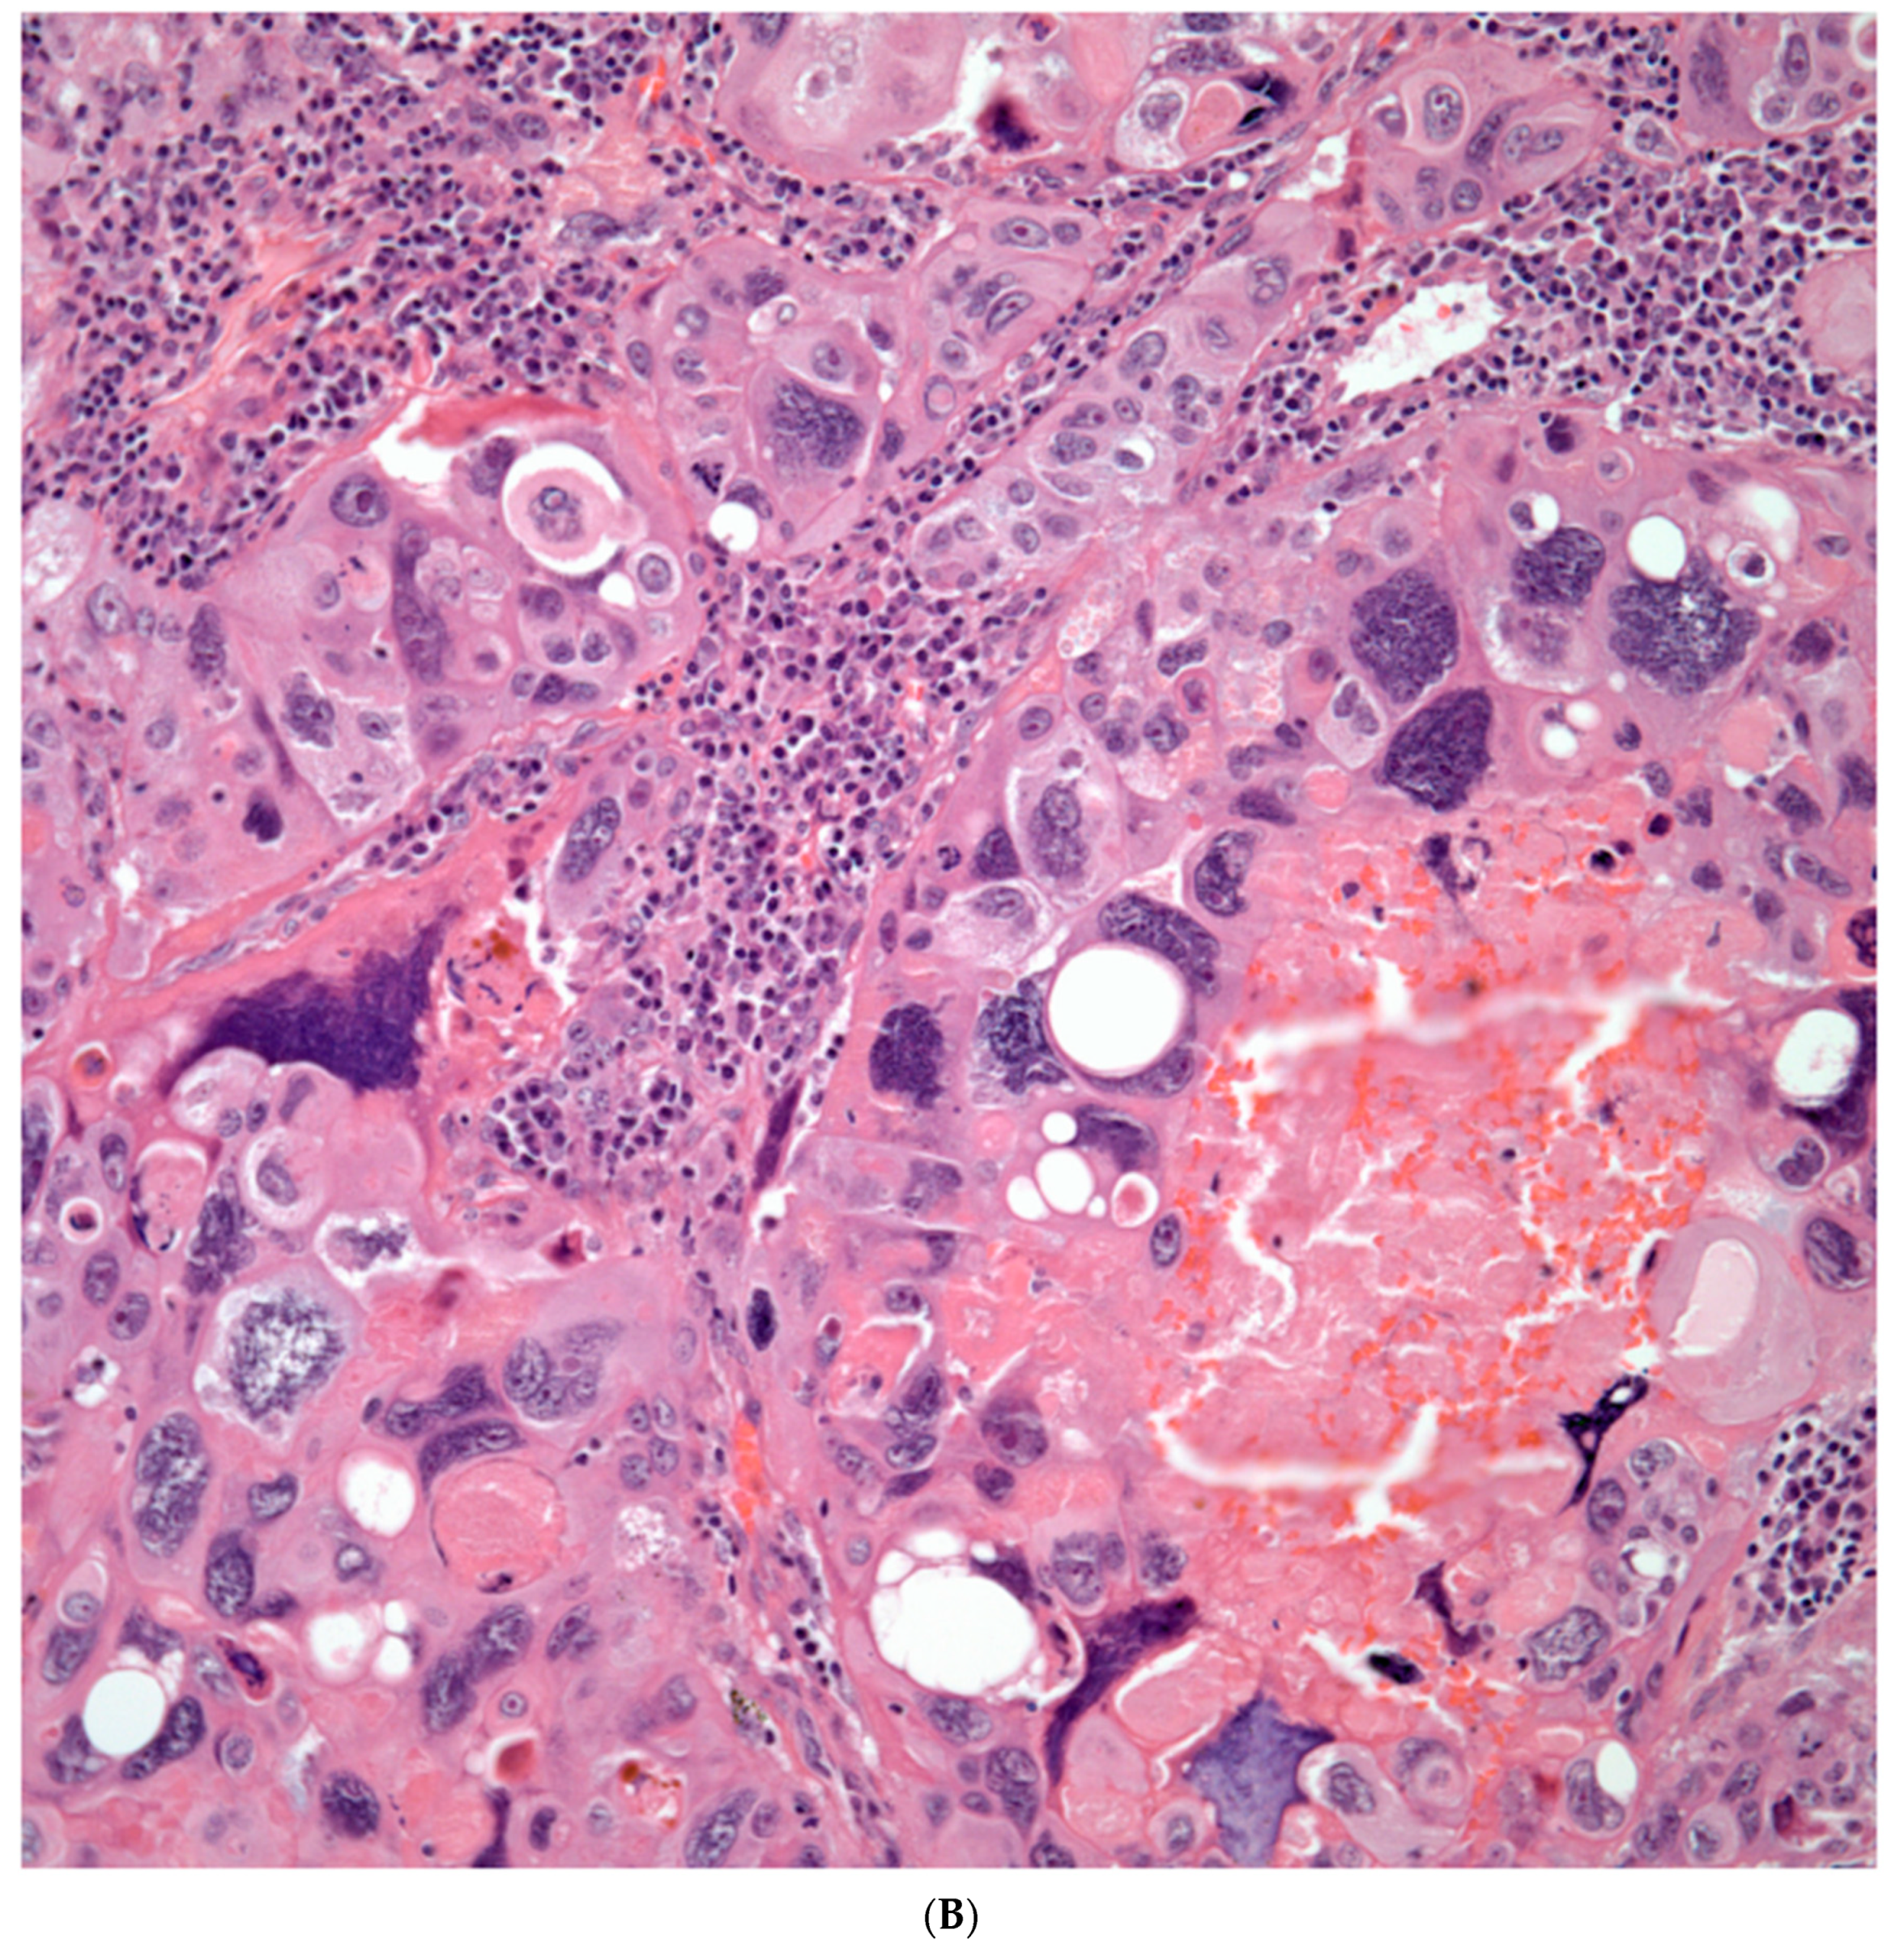

Sarcomatoid carcinomas: these tumors show a tightly packed spindle cell proliferation composed of slender cells with fusiform nuclei and inconspicuous nucleoli, replacing normal lung parenchyma. The tumors are well delimited but not encapsulated (Figure 1). Cellular atypia is variable and may show areas of mild to moderate to marked atypia. Mitotic figures also vary and may be inconspicuous or may be evident with the presence of atypical mitotic figures (Figure 2A,B). In high grade tumors, the presence of necrosis and hemorrhage is prominent and is mixed with the neoplastic component. Important to recognize is that sarcomatoid carcinomas may be associated with areas of otherwise conventional non-small cell carcinoma such as adenocarcinoma or squamous cell carcinoma (Figure 3A,B). In addition, sarcomatoid carcinoma may also show the presence of bizarre giant cells admixed with the spindle cell component (Pleomorphic carcinoma) (Figure 4).

Figure 3. A) Sarcomatoid carcinoma associated with areas of conventional adenocarcinoma; B) Sarcomatoid carcinoma associated with areas of squamous carcinoma.